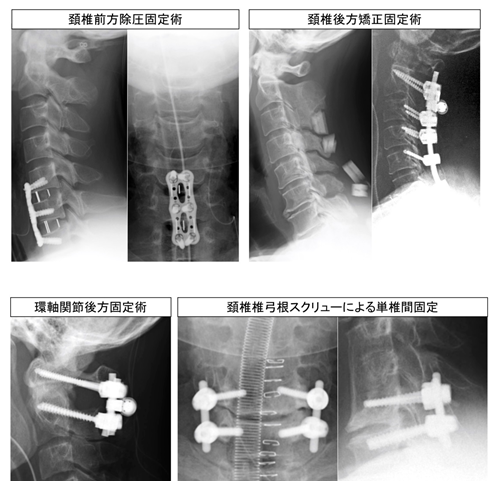

頚椎疾患

薬物治療や、装具療法、ブロック療法(超音波ガイド下)など保存療法でも症状が 改善しない場合、手術を行います。

脊柱管拡大術(椎弓形成術)では、独自にデザインしたスペーサーを用いています。不安定性の生じた症例や変形のある症例では、椎弓根・外側塊スクリューを用いた後方固定術、または前方固定術などを施行し、良好な成績を得ています。